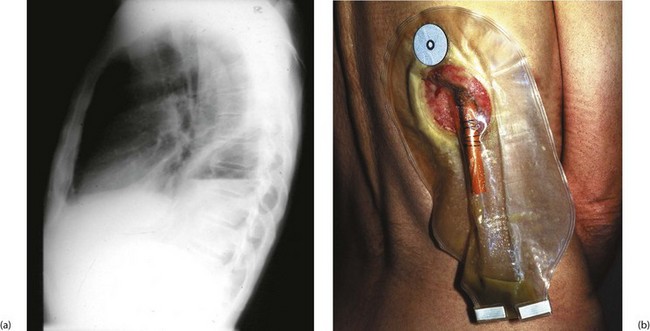

Fig. 31.10 Empyema thoracis

This 51-year-old man underwent a thoraco-abdominal oesophagogastrectomy for proximal gastric cancer. He suffered a small intrathoracic anastomotic leak and developed an intrapleural empyema, shown by the fluid level in (a). (b) Drainage of empyema. A section of rib overlying the cavity was resected and a large red rubber tube was inserted to give dependent drainage into a bag. The drain was gradually shortened as the cavity closed. This patient was alive and well 15 years later